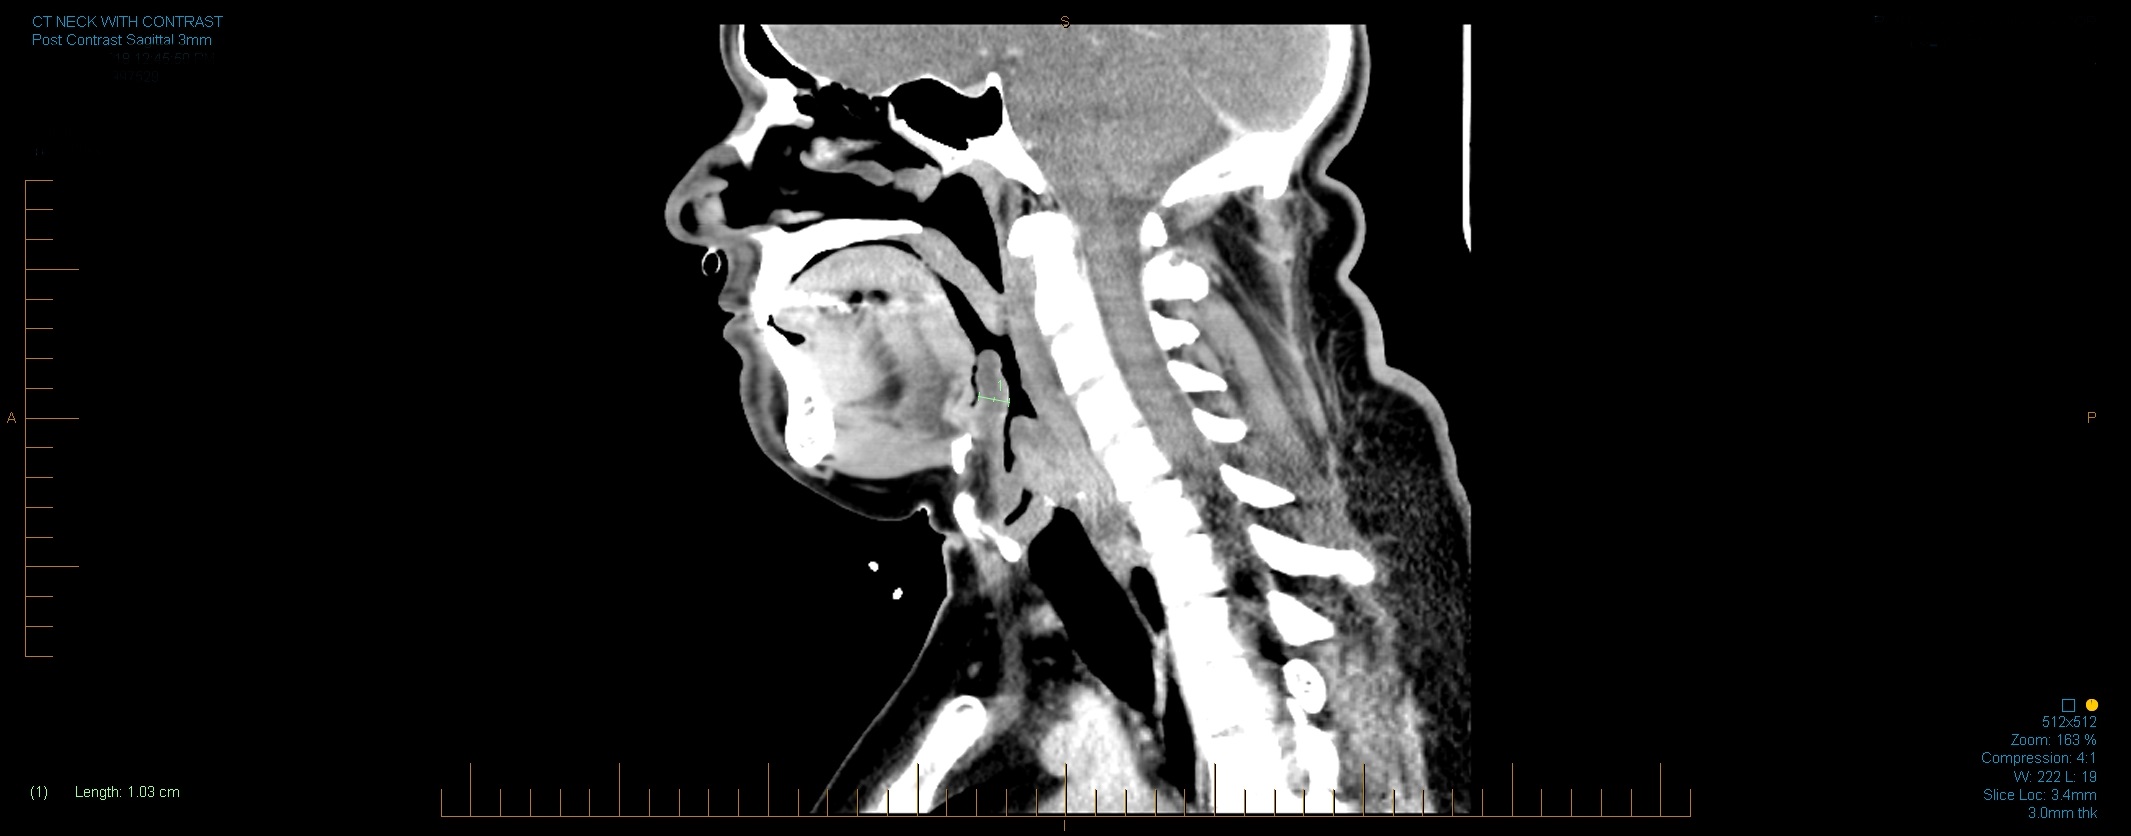

Inflammation of the epiglottis is known as epiglottitis. Epiglottitis is mainly caused by Haemophilus influenzae. A person with epiglottitis may have a fever, sore throat, difficulty swallowing, and difficulty breathing. For this reason, acute epiglottitis is considered a medical emergency, because of the risk of obstruction of the pharynx. Epiglottitis is often managed with antibiotics, racemic epinephrine (a sympathomimetic bronchodilator that is delivered by aerosol), and may require tracheal intubation or a tracheostomy if breathing is difficult. Behind the root of the tongue is an epiglottic vallecula which is an important anatomical landmark in intubation.The incidence of epiglottitis has decreased significantly in countries where vaccination against Haemophilus influenzae is administered.